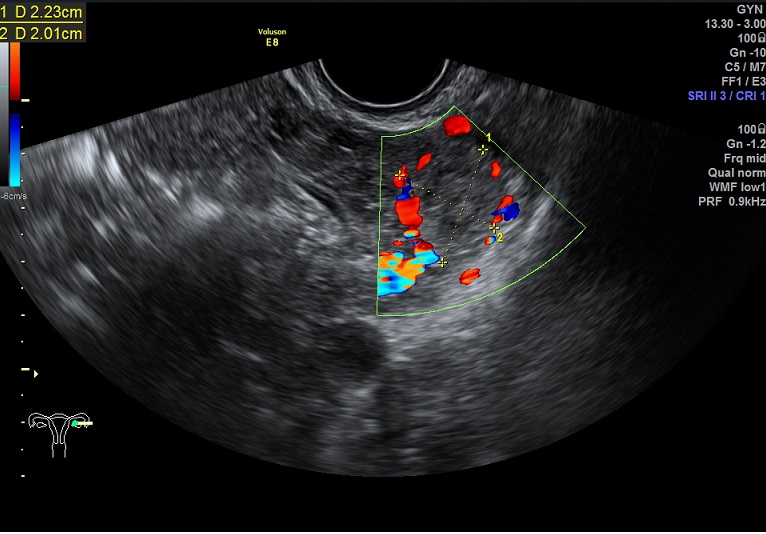

2015-3-19 月经第24天检查 内膜厚0.6cm 内膜血流:1级 内膜波动不明显 左卵巢黄体 子宫动脉: L:PSV:27.3cm/s EDV:4.7cm/s RI:0.83 S/D:5.8 PI:2.5 R: PSV:28.8cm/s EDV:2.0cm/s RI:0.93 S/D:14.4 PI:3.8 舒张早期血流缺失 检验: 2015-3-11 E2: 155.42 LH: 7.00 FSH: 4.43 P: 2.45 |

2015-3-19图示